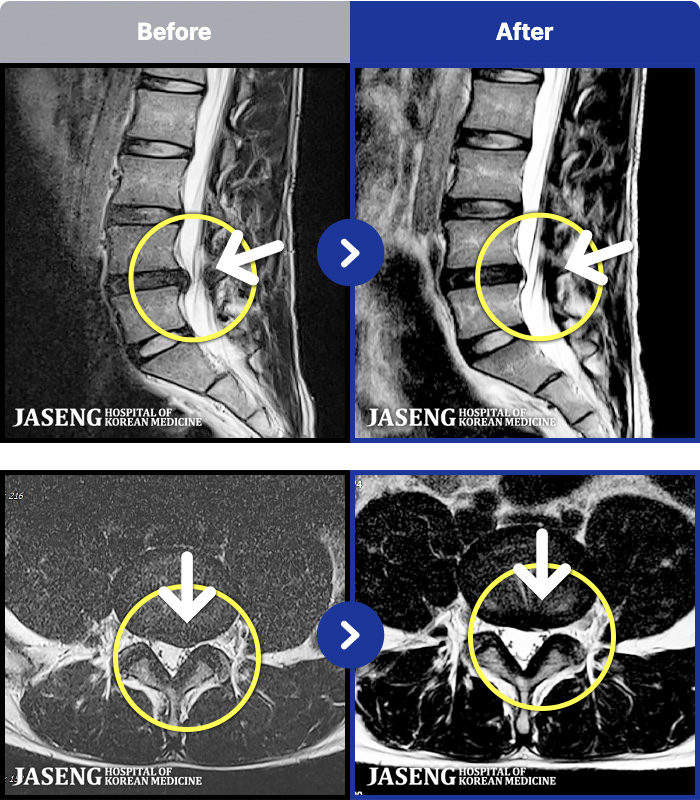

MRI ġ

MRI ũ ʸ Ȯϼ.

㸮 ؼ ̱ ư ϴ.